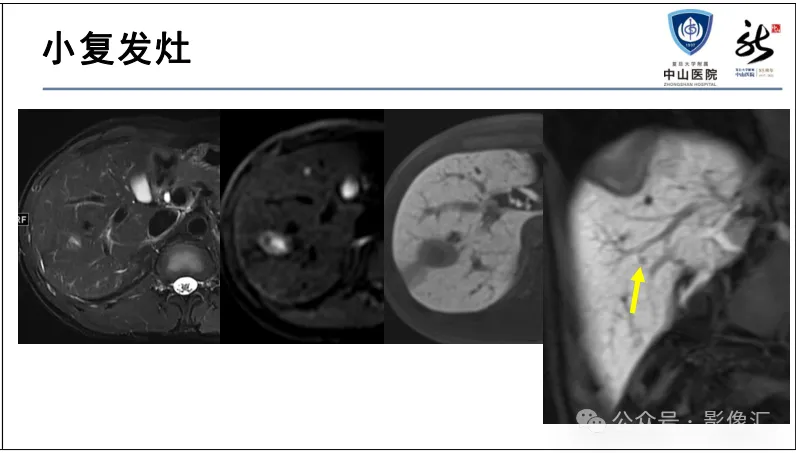

肝胆特异性对比剂增强肝胆图像判读方法与策略,课件来源于网络,作者复旦大学附属中山医院放射科饶圣祥教授。